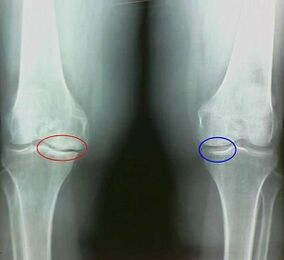

La artrosis es un proceso degenerativo-distófico asociado con la destrucción del tejido del cartílago de la articulación. El cartílago se destruye gradualmente, seca, la distancia entre los huesos de la articulación disminuye, que es la causa del dolor. En formas severas, la destrucción afecta a los huesos. Se vuelven más porosos, pierden su densidad, se vuelven frágiles.

Por ejemplo, ¿cuál es la diferencia entre la artritis y la artrosis de la articulación de la rodilla? Con la artritis, se produce la capa sinovial de los tejidos articulares. Esto causa un aumento de la temperatura en la articulación.

La articulación aumenta, se desarrolla un síndrome de dolor persistente, que se intensifica durante el movimiento. Con la artrosis, el dolor ocurre solo después de la actividad física, puede escuchar un crujido o clics característico en la articulación, gradualmente la articulación se deforma y pierde movilidad.

Como puede ver, las diferencias en los síntomas son insignificantes: en ambos casos hay dolor, rigidez y fatiga. La artritis y la artrosis pueden afectar diferentes articulaciones en el cuerpo humano. Con el daño a la columna y los discos intervertebrales, se desarrolla la osteocondrosis, es similar a la artrosis. Dependiendo del lugar de la enfermedad, se distingue la artrosis del tobillo, el hombro, las articulaciones de la cadera, etc.

Los detalles de los síntomas y el diagnóstico diferencial ayudarán a determinar con precisión la patología: artritis o artrosis.